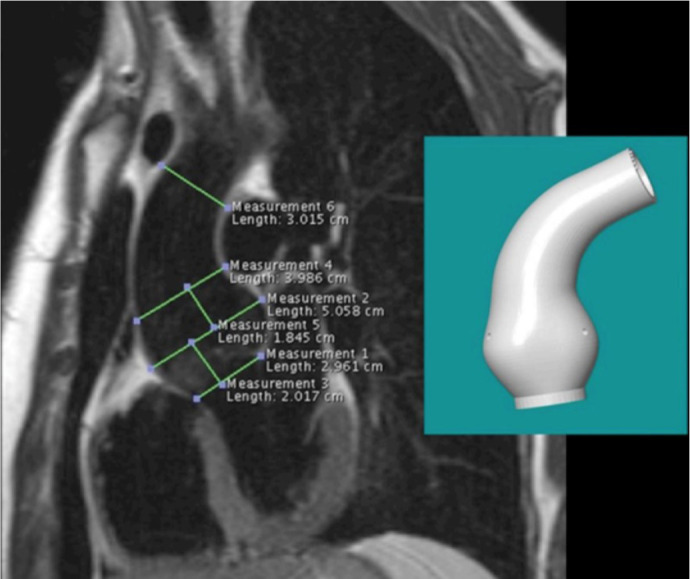

Methods: This report presents the initial clinical experience with the ExoVasc® PEARS implant in the Americas, encompassing 10 patients (six males, age range 30 - 52 years, mean age 37.8 years) diagnosed with aortic root aneurysms. Indications for PEARS included Marfan syndrome (eight patients, including one reoperation), bicuspid aortic valve (two patients, including one with anomalous coronary artery), and associated valvular dysfunction. Cardiopulmonary bypass was utilized in four cases.